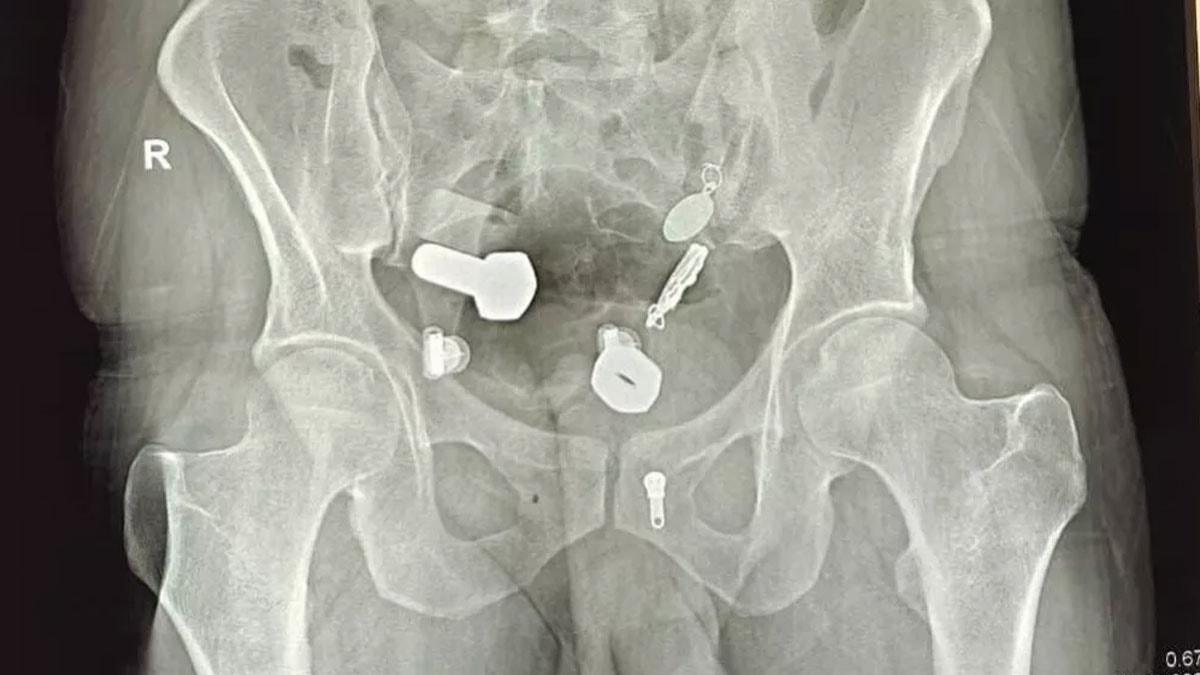

Hindistan'ın Jaipur kentindeki Sawai Mansingh Hastanesi'ne 9 Ekim'de kaldırılan hasta, günlerdir süren mide ağrısı nedeniyle yemek yiyemediğini ve su içemediğini söyledi. Yapılan taramada doktorlar, adamın yemek borusunda bir kol saati, bağırsaklarında ise metal parçaları, cıvata ve somunlar olduğunu fark etti.

Cisimler önce endoskopiyle çıkarılmak istense de başarısız olundu, ardından üç saat süren bir ameliyatla alındı. Cerrahlar, karnına yapılan küçük bir kesiden tüm metal objeleri tek tek çıkardı. Operasyonun görüntüler, hastane personelini bile şaşkına çevirdi.